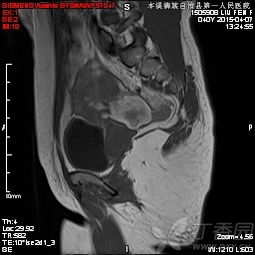

6、盆腔內(nèi)病變:包括膀胱、前列腺、子宮、卵巢、直腸良、惡性占位病變,特別是前列腺增生,子宮內(nèi)膜異位癥等。MRI多方位、大視野成像可清晰地顯示盆腔的解剖結(jié)構(gòu)。尤其對女性盆腔疾病具有重要診斷價值,對盆腔內(nèi)血管及淋巴結(jié)的鑒別較容易,是盆腔腫瘤、炎癥、子宮內(nèi)膜異位癥、轉(zhuǎn)移癌等病變的最佳影像學(xué)檢查手段。